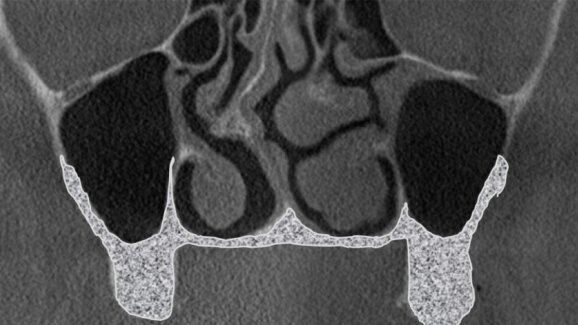

Anatomiczna klasyfikacja została stworzona na podstawie analizy 200 obrazów tomografii wolumetrycznej u pacjentów z całkowitym bezzębiem lub z brakami skrzydłowymi. Każde z tych badań (CBCT) obejmowało 2 zatoki szczękowe: lewą i prawą. Jest to klasyfikacja ułatwiająca podjęcie decyzji, która z metod podnoszenia zatoki szczękowej będzie dla pacjenta odpowiednia i czyli pomaga w doborze metody do przypadku.

Klasyfikację oparto na obrazie z tomografii, jaki uzyskuje się w przekrojach czołowych (wieńcowych) lub prostopadłych do krzywej panoramicznej ułożonej równolegle do łuku zębowego górnego. Klasa „zero” (Tab. 1) została wyróżniona jako sytuacja kliniczna, w której brak bezwzględnych wskazań do zabiegu podniesienia dna zatoki szczękowej z 2 powodów:

Kolejne klasy wyróżnia się na podstawie grubości kostnej ściany przedsionkowej zatoki lub podniebiennej. Jeżeli ściana przedsionkowa jest cieńsza niż podniebienna, wówczas w domyśle łatwiejszy dostęp jest od przedsionka, więc przypadek klasyfikuje się do klasy pierwszej.

Występują jednak sytuacje, kiedy to w badaniu CBCT zauważamy jednakowej grubości ścianę przedsionkową oraz podniebienną. Jest to sytuacja, w której przypadek przyporządkowujemy do klasy drugiej.

W chwili, gdy ściana podniebienna jest cieńsza niż policzkowa, występuje klasa trzecia. U tego samego pacjenta może wystąpić anatomicznie klasa pierwsza po stronie prawej i klasa druga po stronie lewej. Różnice te związane są z takimi czynnikami, jak: